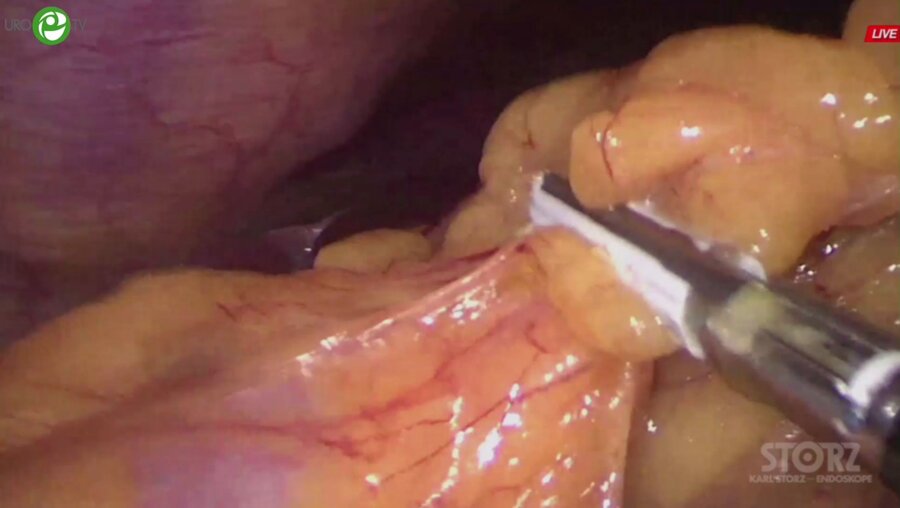

Эндовидеохирургия органов брюшной полости, малого таза и забрюшинного пространства v.4.0